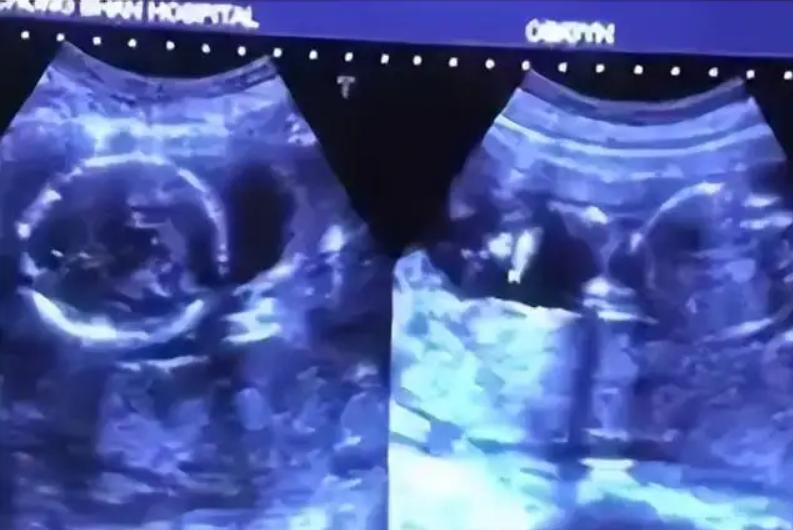

三个月的时候,张建军夫妇到云梦县人民医院做检查,医生高兴地告诉他们检查到了两个胎心,也就是说杨伟怀的是一对双胞胎。

等到怀孕六个月,做排畸检测的时候,医生仔细观察了B超显像许久都没有发现任何问题,只说两个孩子都很健康,安心在家养胎就好了。